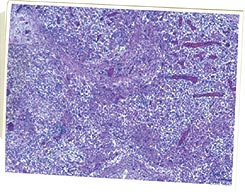

2. Présence de lésions microscopiques caractéristiques dans les organes lymphoïdes : le rapport d’histologie du laboratoire d’analyses mentionne alors une déplétion lymphocytaire avec infiltration histiocytaire (granulomateuse). Il y a une présence variable de cellules géantes multinucléées (au milieu des années 90, ce critère était considéré comme essentiel ; depuis, il n’est que secondaire). La présence d’inclusions intracytoplasmiques est fréquente (si une technique additionnelle est mise en œuvre, il est possible d’observer que ces agrégats contiennent du PCV2).

3. Détection de PCV2 dans les lésions des tissus lymphoïdes typiques (point 2), chez cet animal (point 1), par une technique qui permet d’estimer la quantité de PCV2 (ses protéines, par immunomarquage, ou son génome, par hybridation in situ), et de l’associer à l’intensité des lésions.

Ce diagnostic individuel doit donc faire appel au laboratoire d’analyses. Plusieurs organes lymphoïdes peuvent être prélevés car les lésions de MAP se retrouvent dans l’ensemble de ce système : ganglions mésentériques, amygdales…